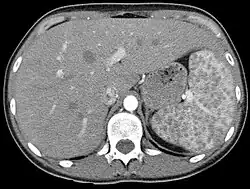

In einer großen amerikanischen Fallserie von 2001[9] zeigten sich eine Beteiligung von Lungen und mediastinalen Lymphknoten bei 95 %, die Haut war in 24 % beteiligt, es folgten extrathorakale Lymphknoten in 15 %, Augen in 12 % und Leber in 12 %. Aber prinzipiell können alle Organe beteiligt sein, auch Milz und Knochenmark.

Eine Lungenfunktionsprüfung, meist auch eine Röntgenaufnahme der Lunge sowie eine Computertomographie werden durchgeführt, um die Therapiebedürftigkeit abschätzen zu können. Eine bronchoalveoläre Lavage (BAL) mit Zytologie kann oft diagnoseweisend sein. Sie zeigt typischerweise eine lymphozytäre Alveolitis mit Zunahme des CD4/CD8-Quotienten durch Erhöhung der Zahl der T-Helferzellen. Der Quotient beträgt beim Gesunden ca. 2, bei akuter Sarkoidose > 5. Eine transbronchiale Lungenbiopsie oder durch endobronchialen Ultraschall (EBUS) gezielte transbronchiale Biopsie der vergrößerten mediastinalen Lymphknoten kann histopathologisch zur Diagnosesicherung beitragen. Dabei werden in den Präparaten insbesondere nicht-verkäsende, epitheloidzellige Granulome mit Langhansschen Riesenzellen und einem Randwall aus Lymphozyten, Monozyten und Fibroblasten beobachtet. Das histologische Bild ist allerdings nicht spezifisch für die Sarkoidose. Die früher durchgeführte 67Ga-Szintigrafie wurde durch die FDG-PET/CT-Untersuchung abgelöst. Sie dient einerseits zur Kontrolle der Effektivität der durchgeführten Therapie, andererseits kann mit einer Untersuchung ein Überblick über die Anzahl der betroffenen Organsysteme gewonnen werden.